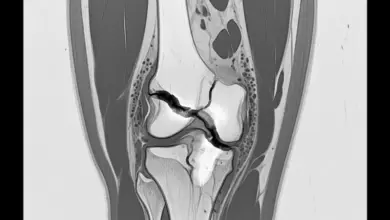

É por isso que a decisão cirúrgica depende de uma avaliação criteriosa, levando em conta exame físico, sintomas, ressonância magnética, localização da ruptura, qualidade do tecido e perfil do paciente.

A decisão não deve ser tomada com base apenas na ressonância. O laudo ajuda, só que a indicação real nasce da soma entre exame clínico, idade biológica, padrão da lesão, queixa do paciente e demanda funcional.